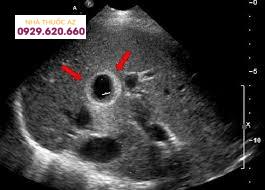

Những hình ảnh tổn thương ung thư gan trên siêu âm gồm:

Ung thư gan nguyên phát là một thương tổn có hình dạng đa dạng, cụ thể:

Với ung thư nguyên phát nhỏ dưới 3cm thường có dạng nốt, bờ giới hạn không rõ ràng, nốt này có thể tăng âm hoặc giảm âm so với nhu mô gan, nhưng chủ yếu là các nốt giảm âm. Doppler mạch có tăng sinh mạch máu trong khối u, với hình ảnh tưới máu điển hình là hình ảnh mạng lưới dòng chảy nhỏ từ quanh khối đi vào các phân nhánh trong khối.Với những khối u trên 3cm: Có thể gặp dạng nốt với những nốt có ranh giới rõ ràng, cấu trúc âm không đều và có viền giảm âm xung quanh; Dạng thâm nhiễm điển hình bởi khối có ranh giới khối u không rõ, xâm lấn các khu vực xung quanh, xâm lấn tĩnh mạch cửa và đè đẩy tổ chức xung quanh; Một dạng lan tỏa, thấy các nốt rải rác trong gan, kích thước nhỏ, dạng này hiếm gặp.Ung thư biểu mô đường mật: Ít gặp, tổn thương trên siêu âm thấy khối u có kích thước thường lớn, giới hạn rõ, cấu trúc âm đa dạng, trung tâm có nốt vôi hóa.

Hình ảnh siêu âm ung thư gan